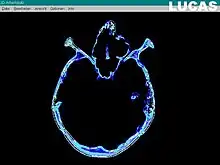

Data from separate bidimensional slices generated by a CT or MRI scan are uploaded into the LUCAS system. The resulting dataset is then processed, in order to eliminate image noise, and to enhance the anatomical contours and also the general contrast of the images. The next step is to create a virtual 3D model from the gathered collection of 2D images. The bone segment that is to be repositioned is marked, on the 3D grid reconstructed model; then, the actual repositioning of that bone segment is done on the virtual model, until the optimal anatomical position is obtained. The criteria for the optimal position of the bone segment are: symmetry with the opposite side, the continuity of the normal bone contours, or the normal volume of an anatomical region (such as the Orbit. Afterwards, a textured final image is rendered. The calculated vectors for the bone segment repositioning, together with the whole virtual model are finally transferred to the Surgical Segment Navigator.